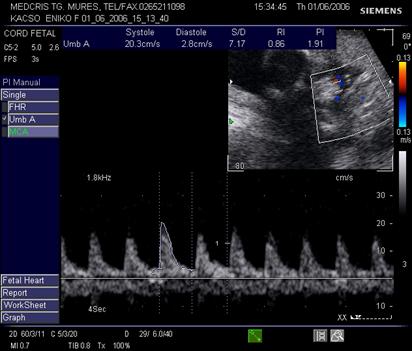

Doppler in circulatia cerebrala

Artera cerebrala medie are directia inainte si in afara, primeste sange din carotide si arterele vertebrale. Planul de reperare este cel al pedunculilor cerebrali, lateral de poligonul Willis. Ea reprezinta sediul preferat pentru velocimetria cerebrala.

In sarcina normala, rezistenta crescuta cerebrala se traduce in velocimetria cerebrala prin diastola scazuta. Aspectul normal al velocimetriei cerebrale permite aprecierea unei stari de bine fetale pentru 2 saptamani [17].

Velocimetria cerebrala , singura, nu aduce informatii asupra hipoxiei din circulatie.

Indicele Arbeille (raport cerebro-placentar) = IR a. cerebrala medie/IR a. ombilicala este supraunitar in conditii de sarcina fiziologica.

In afara fenomenelor de redistribuire a fluxurilor vasculare fetale, amplitudinea vitezelor diastolice la arterele cerebrale ramane inferioara fata de artera ombilicala, deci valoarea indicelui cerebroplacentar este supraunitara. Vasodilatatia cerebrala din redistribuirea fluxurilor sanguine, din suferinta fetala cronica, va determina o scadere semnificativa a IR cerebrala, cu trecerea indicelui cerebroplacentar in valoare subunitara.

Fig. nr. 326. Doppler pe artera cerebrala medie cu diastola crescuta si inversarea indicilor de rezistenta ( indicele Arbeille subunitar ) la fat de 34 sapt cu retard major de crestere intrauterina si sdr genetic